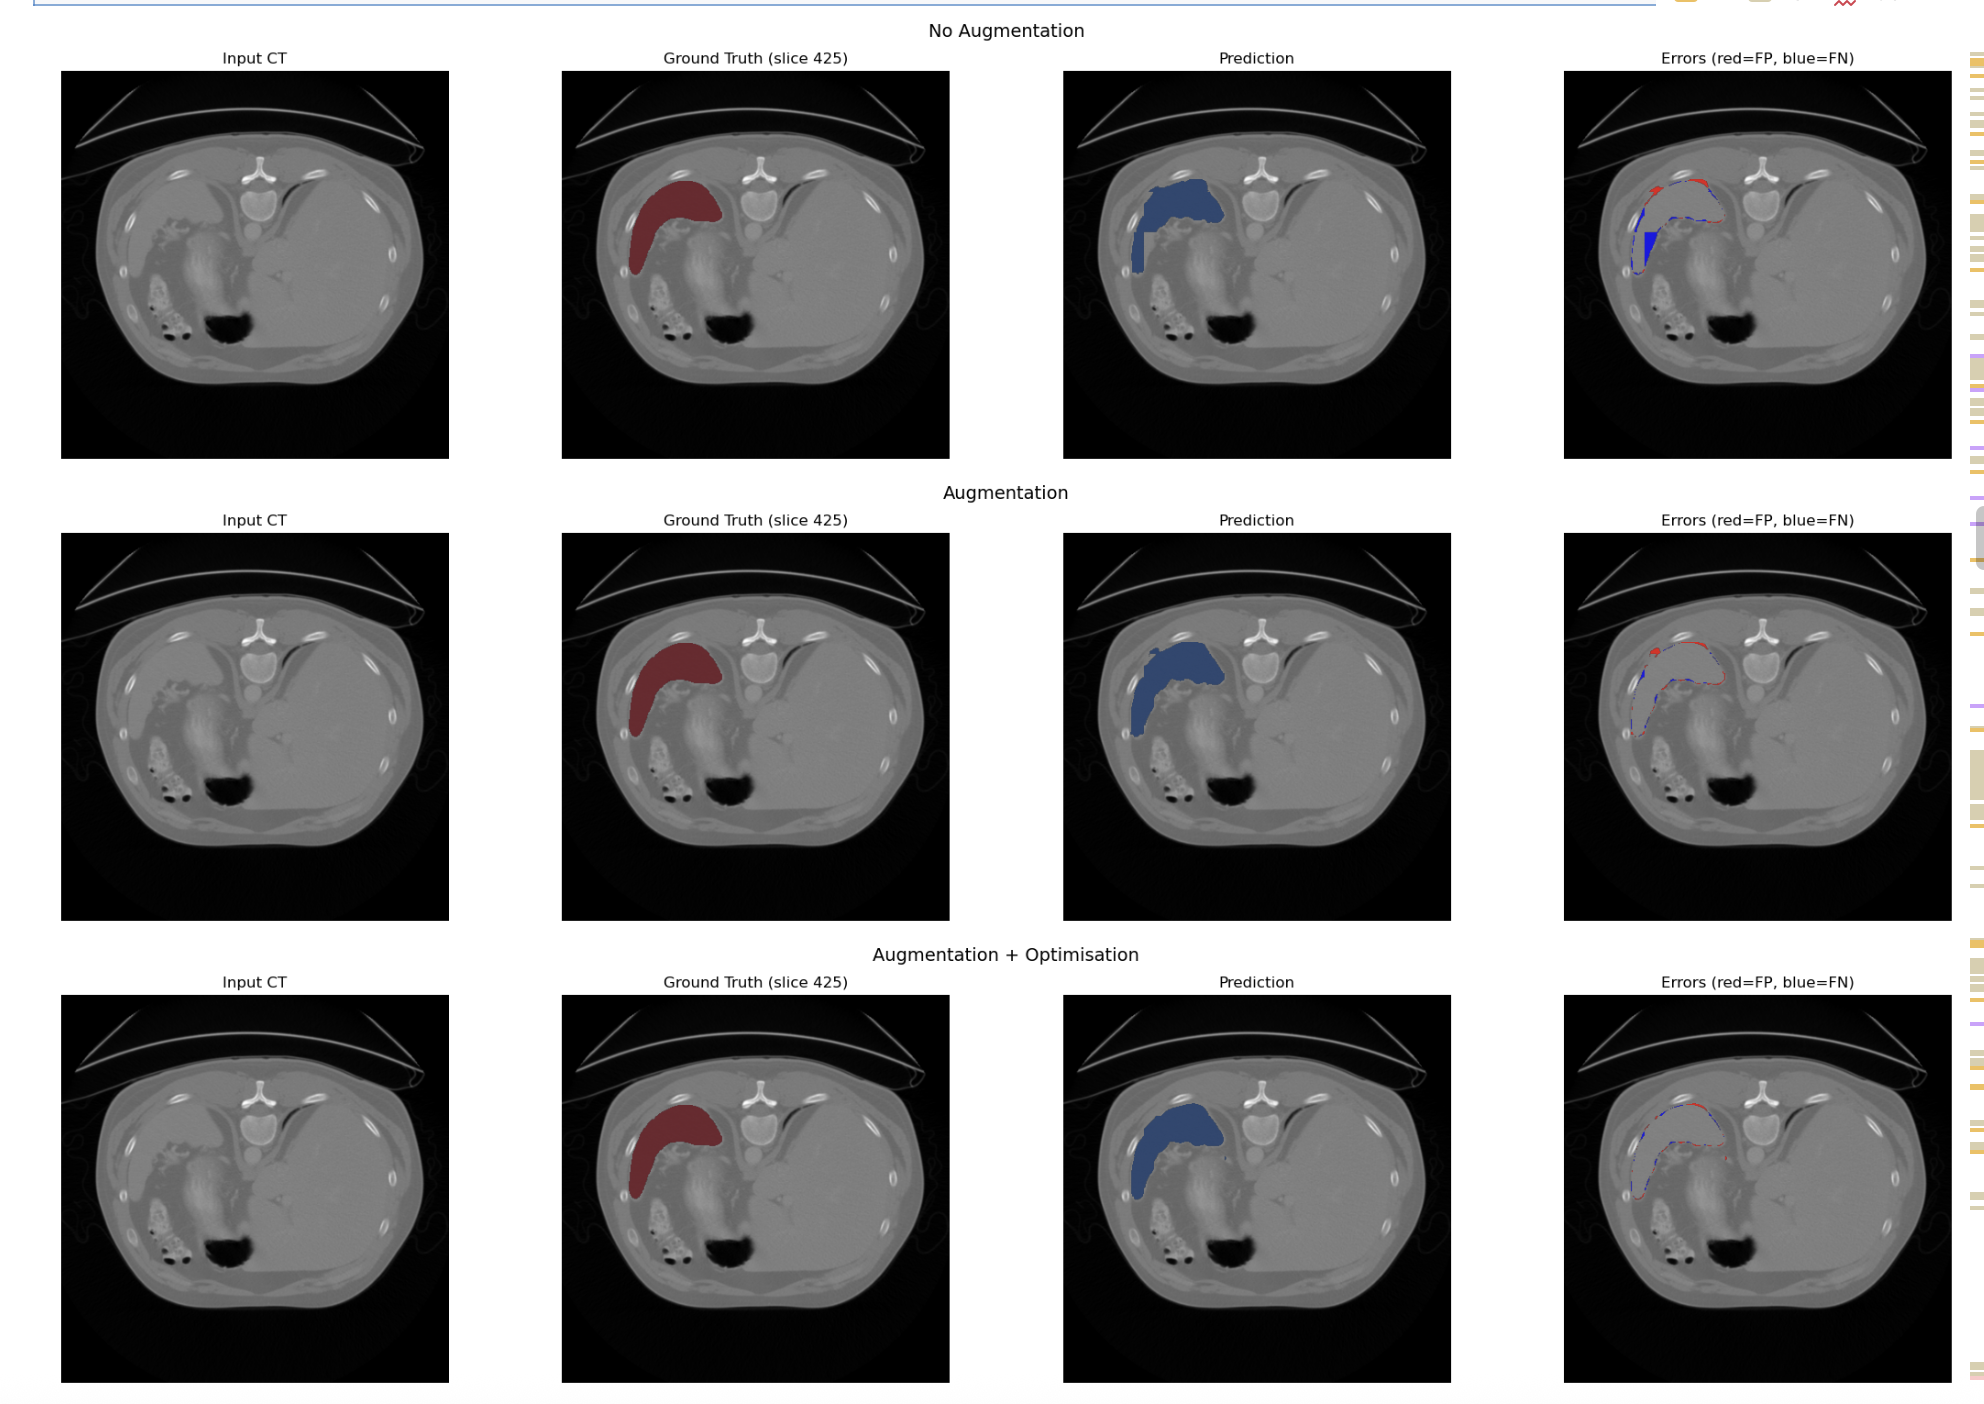

Volumetric Spleen Segmentation via Attention U-Net (2026)

Description: I developed a 3D image segmentation of the Spleen from various CT scans. The model's backbone is based on the Attention U-Net by Oktay et.al. I developed and benchmarked five distinct models against a baseline standard U-Net: Attention U-Net, Attention U-Net with Data Augmentation, Attention U-Net with Data Augmentation & Optimisation, Attention U-Net with an Augmentation Consistency technique, and finally, a Bayesian Attention U-Net.

Tech Stack: PyTorch, Bayesian Deep Learning, Model Ensembling, SimpleITK.